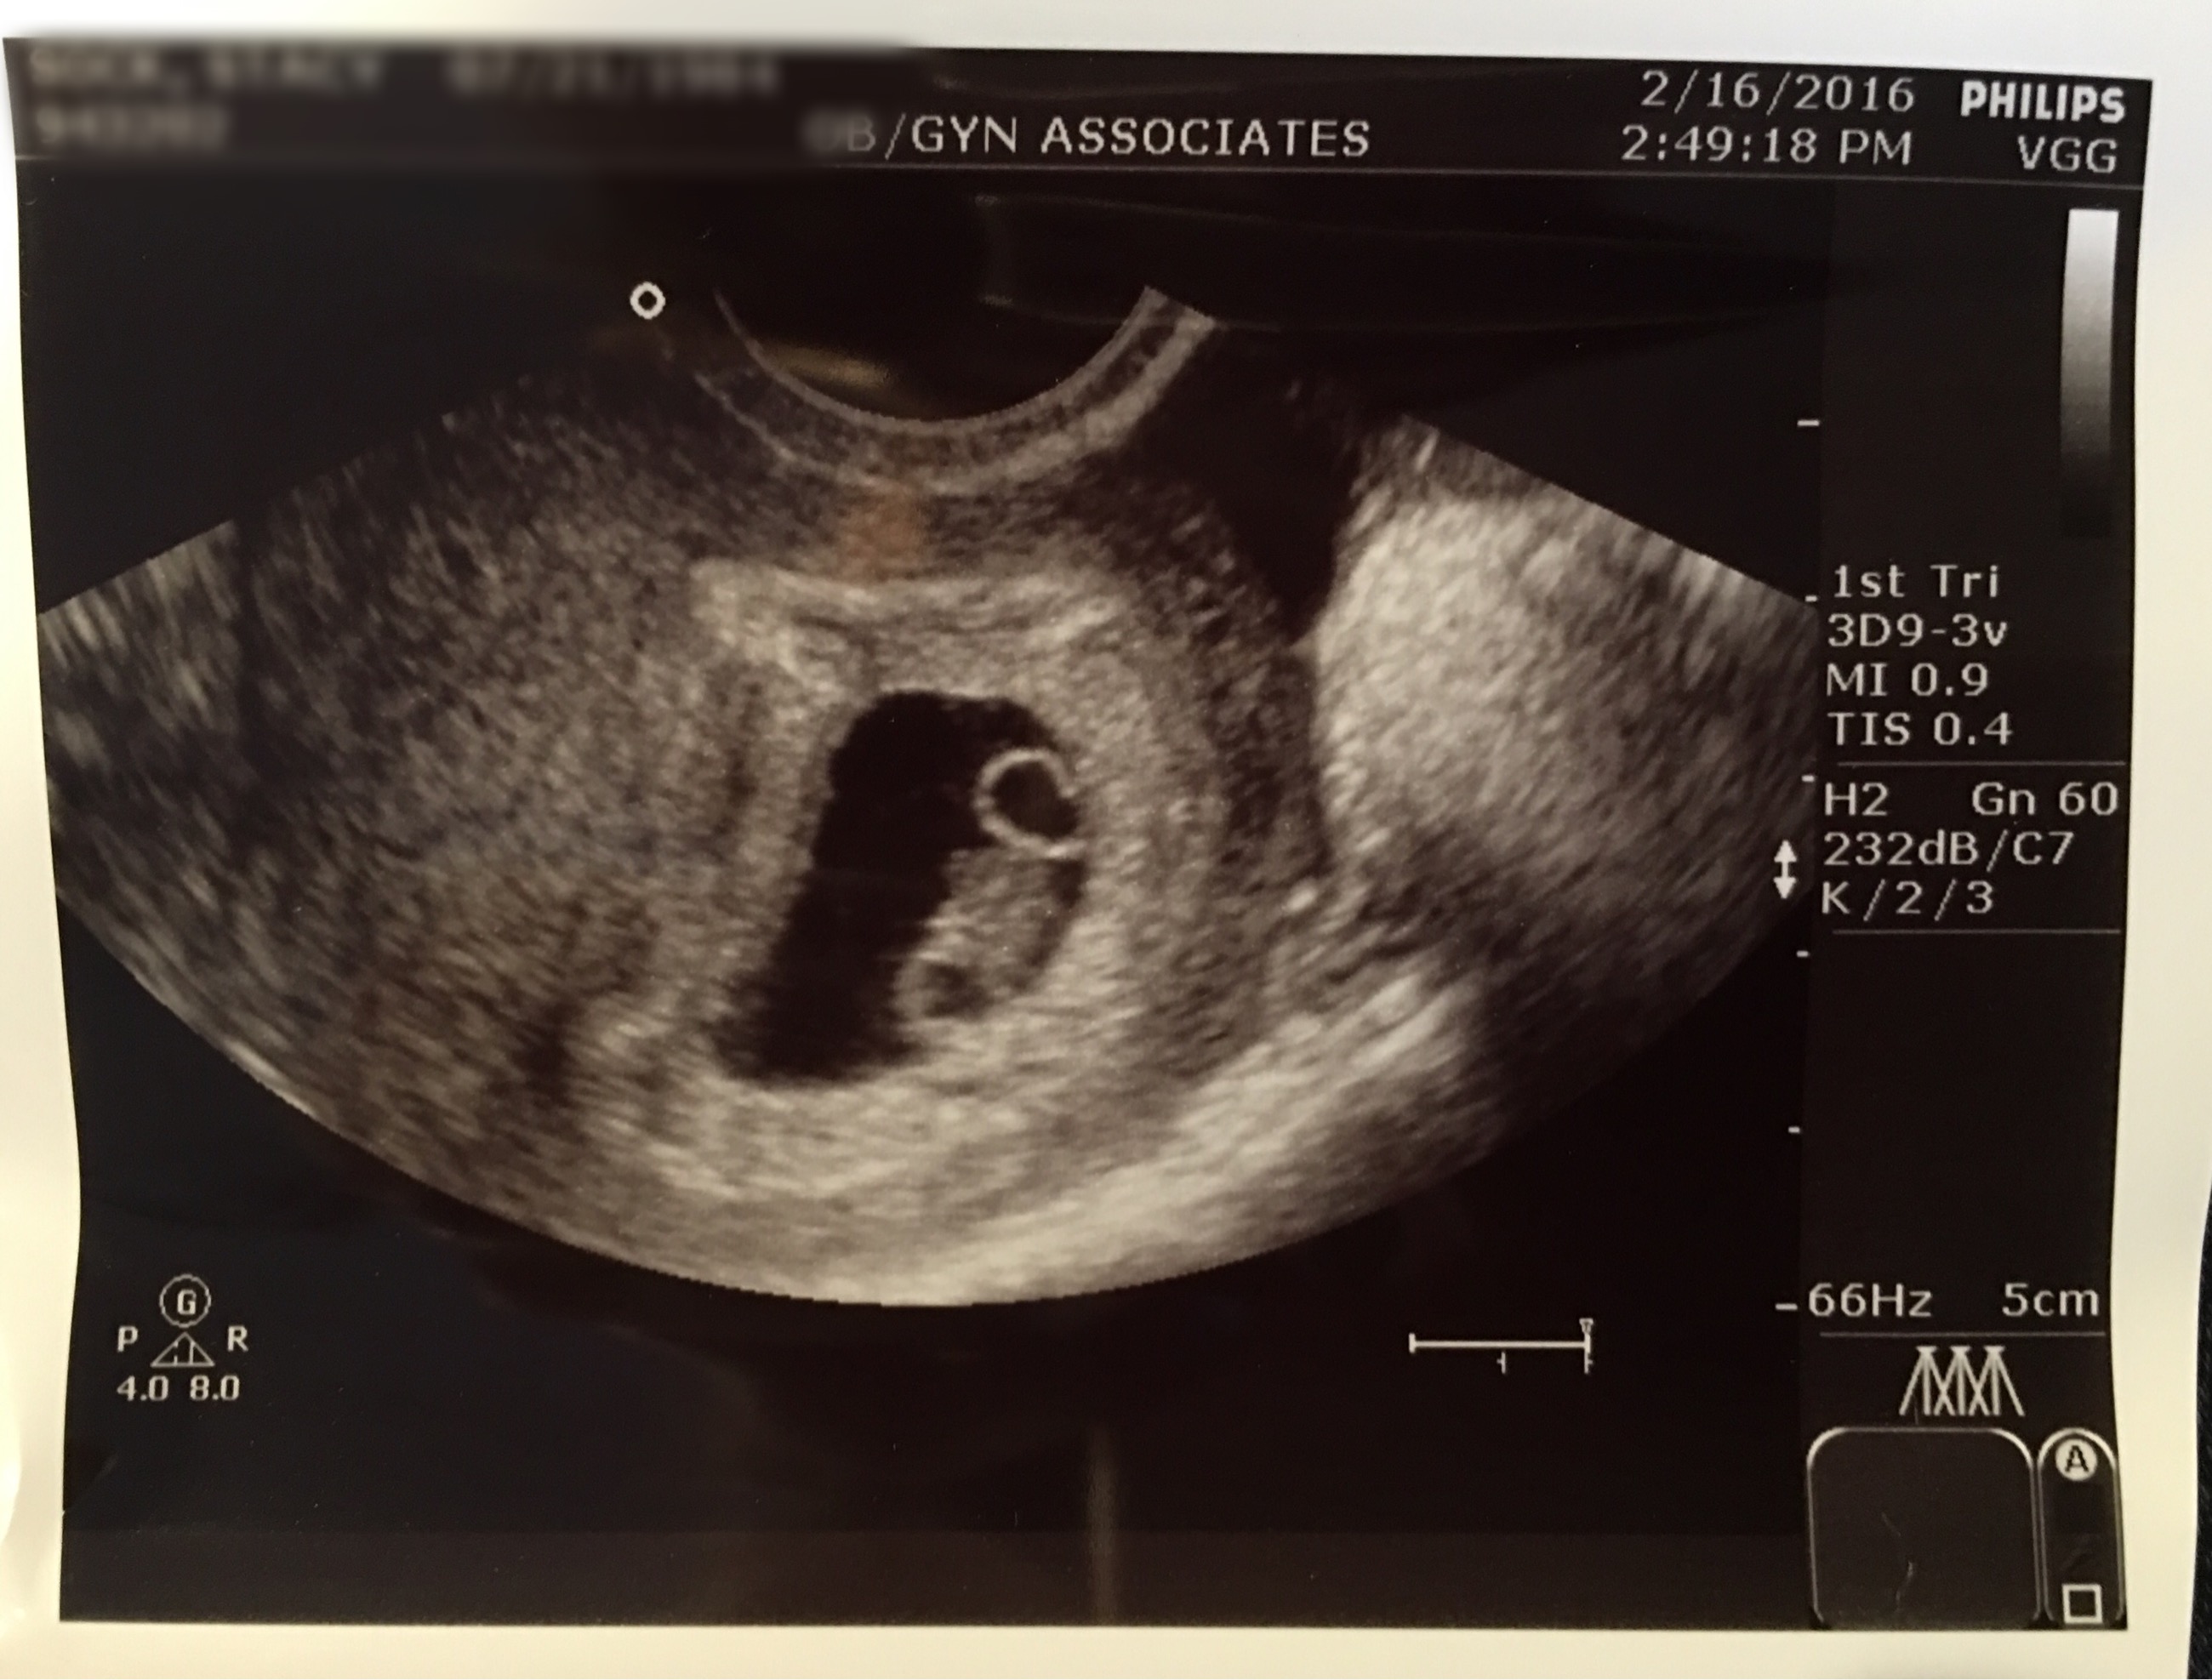

How far along? 8 weeks.

Size of baby: The size of a raspberry.

Best moment the week: Seeing little peanut on the ultrasound again, the heartbeat, hearing GOOD news and of course my Josie started calling me “mommy” instead of “momma”. It’s just so cute how much she’s talking. Oh and she’s starting to crawl around on the floor and meow like a cat. It’s hilarious and super cute!

The circle at the top is the yolk sac. Then baby’s head is at the bottom. HR was 156! Measuring 7w6d at exactly 8w pregnant.

The cyst on my ovary has grown and we hope it doesn’t rupture.